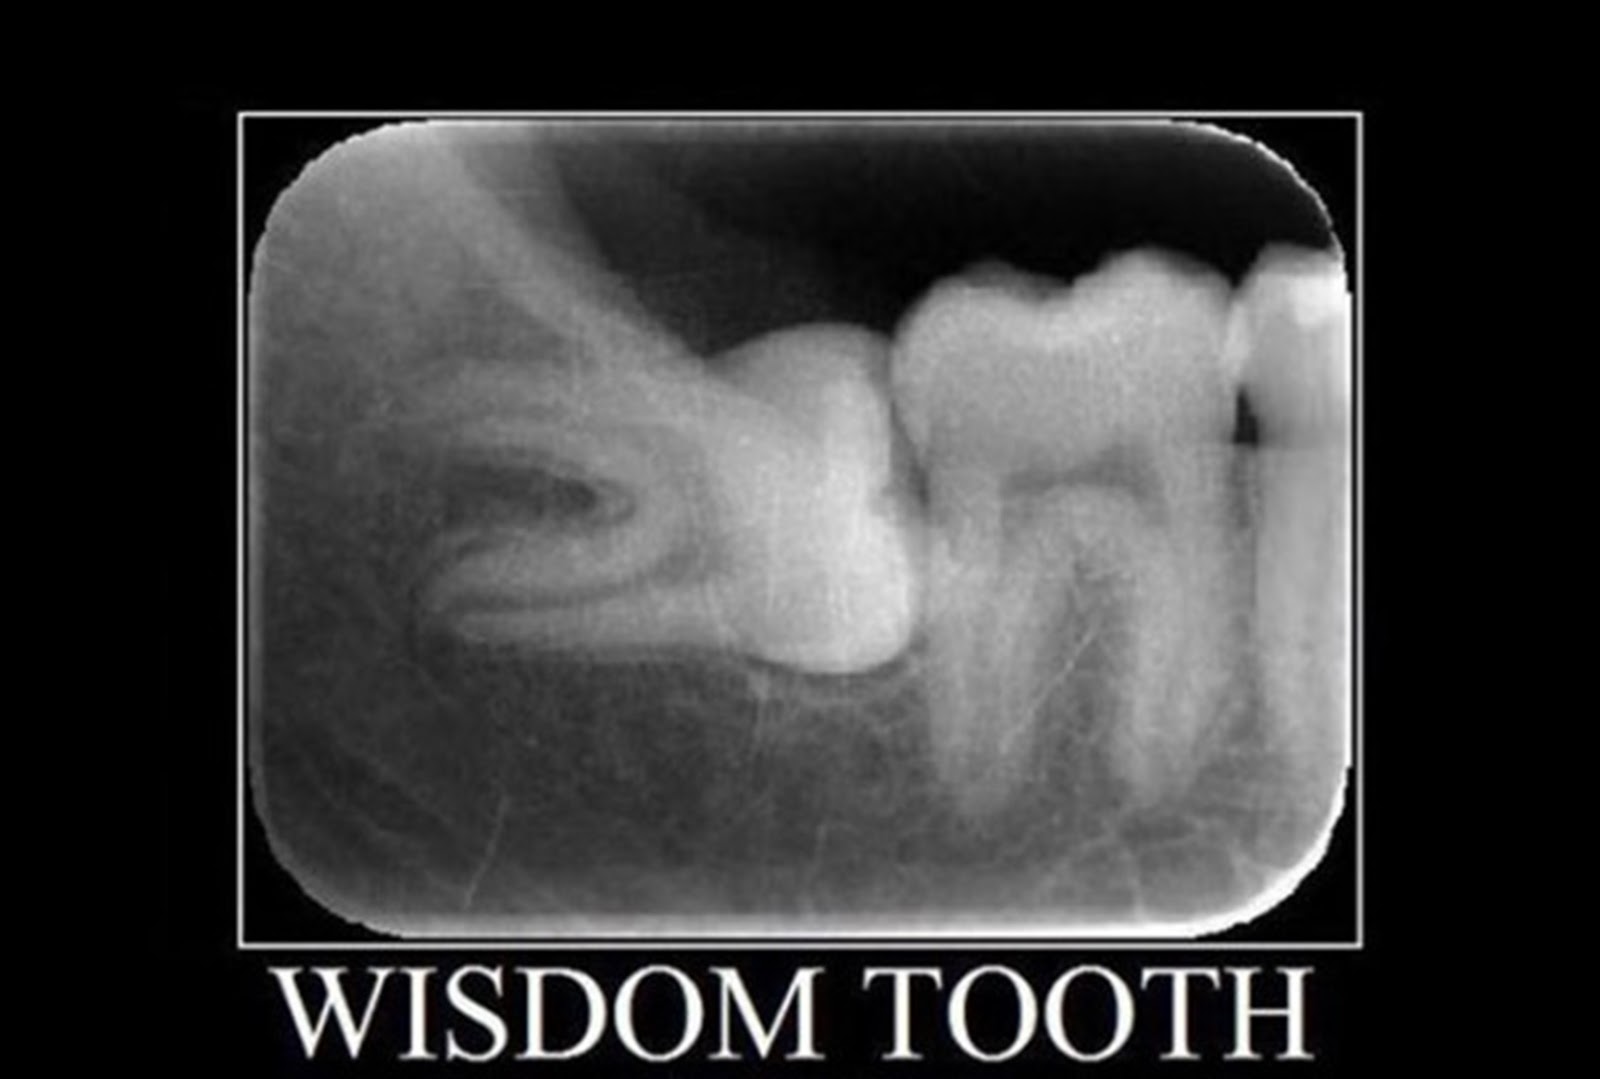

Impacted Wisdom Tooth X-Ray Pt2 By HotheadSquirrel5 On DeviantArt

www.deviantart.comImpacted Wisdom Teeth Panoramic X Ray - TeethWalls

www.deviantart.comImpacted Wisdom Teeth Panoramic X Ray - TeethWalls